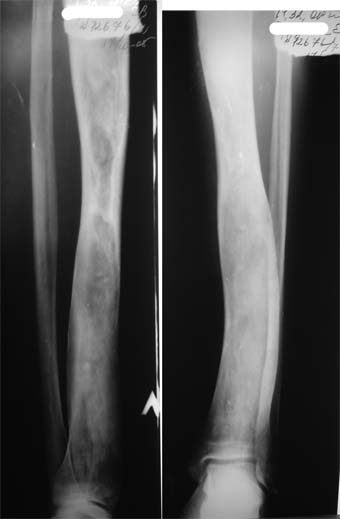

В приложении вид больного и рентгенограммы бедра 2001 год и 2005 год.

2001

2005

В настоящее время имеется умеренный рубцовый процесс правого бедра не мешающий на объем движений в суставах. В коленном суставе слева бедро обычное, голень - булавовидное утолщение проксимального конца большеберцовой кости. На рентгенограммах тотальное поражение кости с увлечением в процесс проксимального эпиметафиза, поражение характерно для болезни Campanatsehi

У больного полиоссальноая форма фиброзной дисплазии с поражение левой бедренной и большеберцовой кости. На рентгенограммах - тотальное разрастание и остончение кортикального слоя. Имеется удлинение левой нижней конечности на 2,5-3 см за счет голени. Больному показано оперативное лечение левой большеберцовой кости.

Пациента напугали, что срочно надо оперироваться, пока не произошел патологический перелом.

А кто напугал - может, пусть и оперируют? А по Вашей оценке, где видно ожидаемый патологический перелом? А ножки уравнять он не хочет?